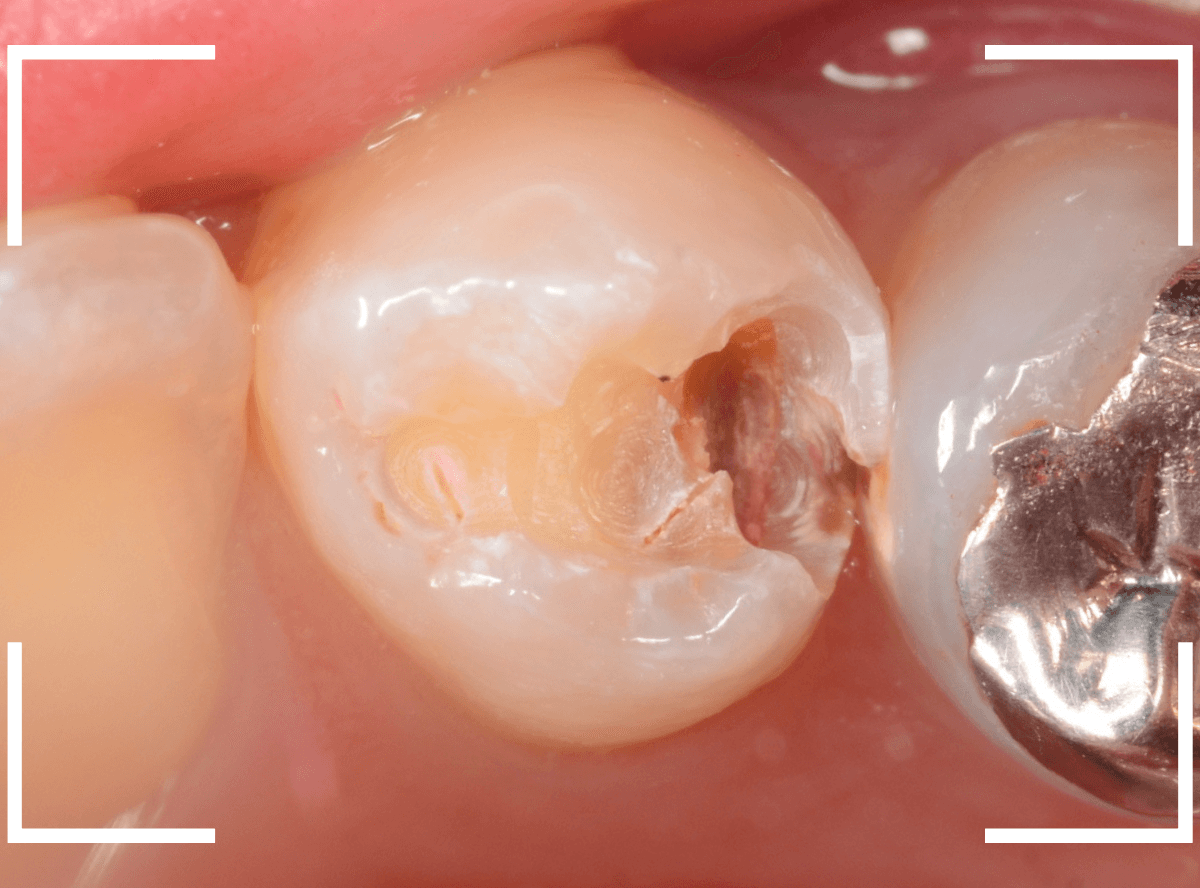

Case.23 歯のすきまから両側が大きな虫歯

「下の奥歯が痛む」という訴えで来院された患者さんのケースです。

目視でも、手前の奥歯がかけていて、中で虫歯が広がってるであろうことは予想できます。

ピンセットで歯を叩いてみても、手前の奥歯が痛むようです。

レントゲン写真で確認します。

青い線が神経、赤い線が虫歯の範囲です。

奥歯の方がより深い虫歯に見えますが、再度打診で確認したところ、やはり手前の奥歯が痛むそうです。

状況から、まず手前の奥歯から治療となりました。

麻酔をして、手前の奥歯のレジンを慎重に外します。

前に虫歯の治療をした時点で、神経スレスレの状態でしたので、削りすぎないように慎重にレジンを外さなければいけません。

レジンを外して、う蝕検知液で確認します。

レジンの中で虫歯が進行していたのがわかります。

慎重に全ての虫歯を除去しました。

何とか、神経が露出せずに済んでいます。

お薬をつめて、セメントで蓋をして経過観察します。

後日、状況を確認したところ、虫歯処置した後も、手前の奥歯が痛むとの事でした。

「我慢できないほどでもない」との事でしたので、引き続き経過観察しつつ、奥歯の治療を治療する事になりました。

奥歯は、レントゲンで見た通り、少し歯を削るとすぐに虫歯の穴が出てきました。

こちらは、ある程度虫歯を取ったところで染め出してみると真っ赤です。

ですが、何とか神経に達する前に、全ての虫歯を除去できました。

神経の治療が必要かと思っていたので、その点は幸運でした。

奥歯もお薬をつめて、セメントで蓋をして経過観察です。

何とか神経を取らずに済ませたいですが、どうなる事か・・・。